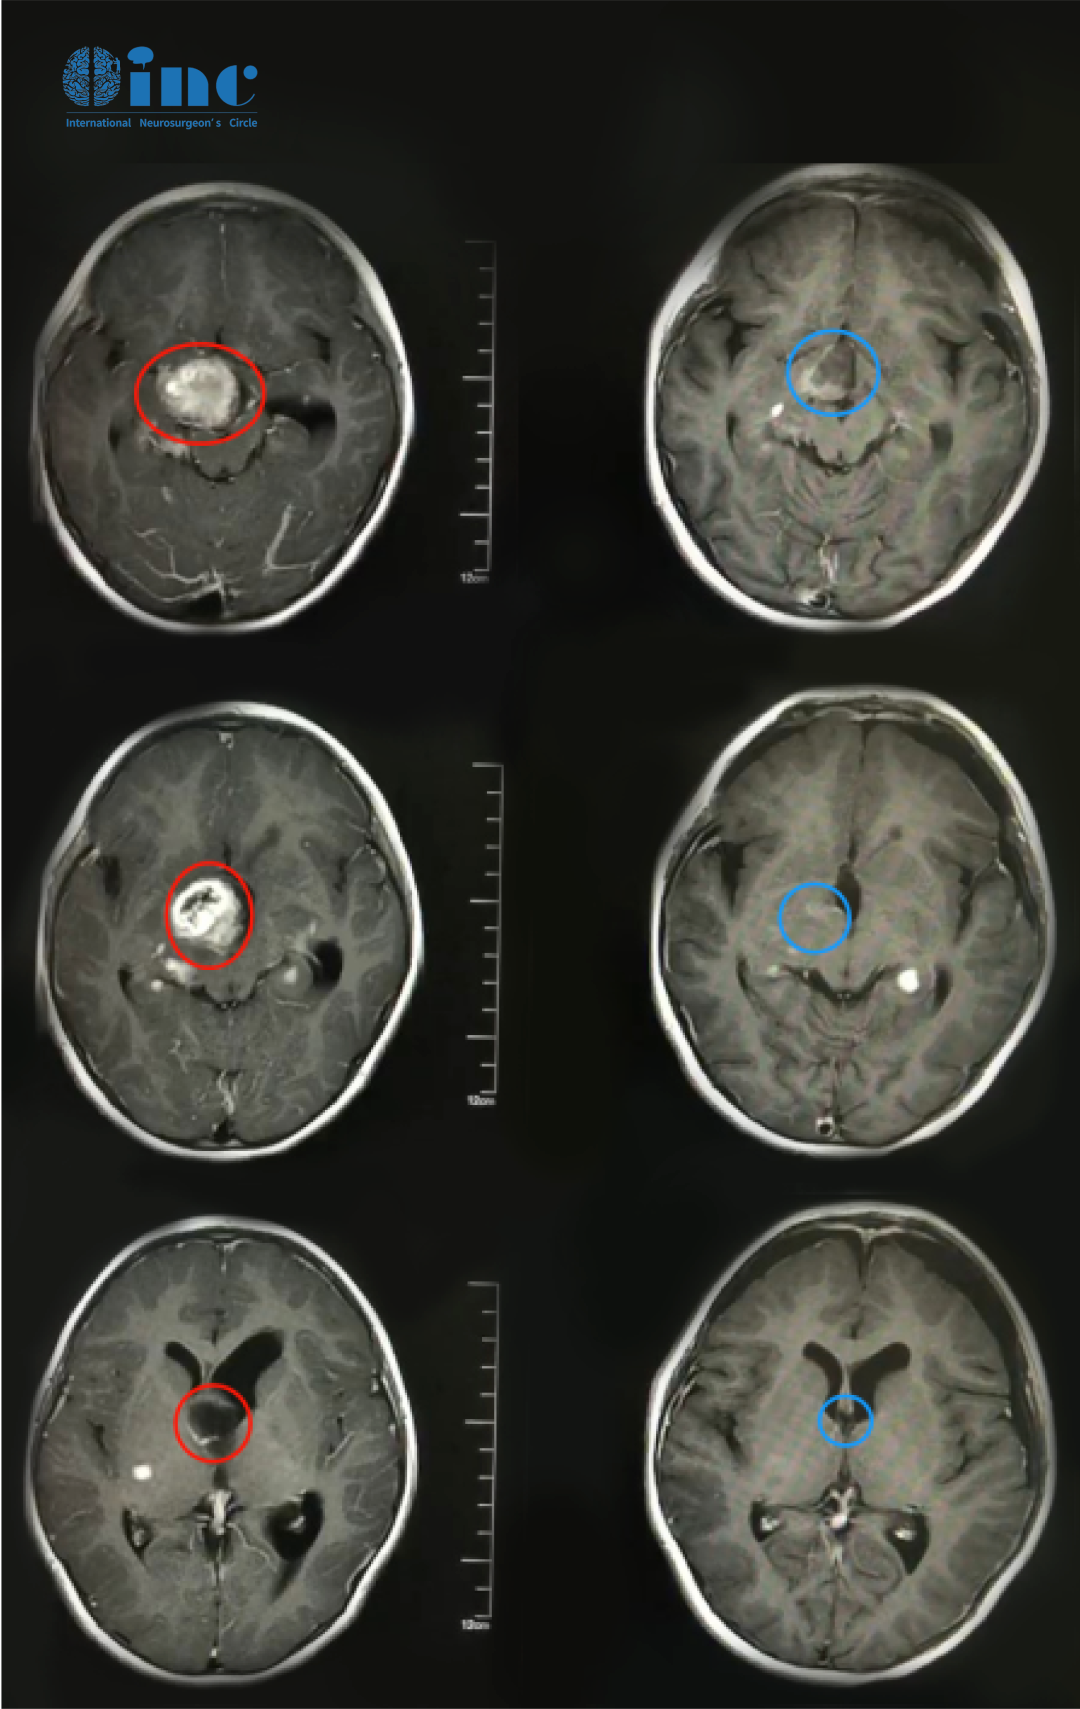

康康术前术后影像对比

幸运的是,康康的父母较后联系到INC国际神经外科医生集团,并咨询成为2021年巴教授来华疑难手术示范的一个病人。在手术中,康康的肿瘤得到了顺利次全切,原有视力得到保留。术后病理结果为毛细胞粘液样型星形细胞瘤,这属于WHO二级胶质瘤,也意味着康康配合术后化疗以及后期的新型放疗可以得到比预期更好的预后。